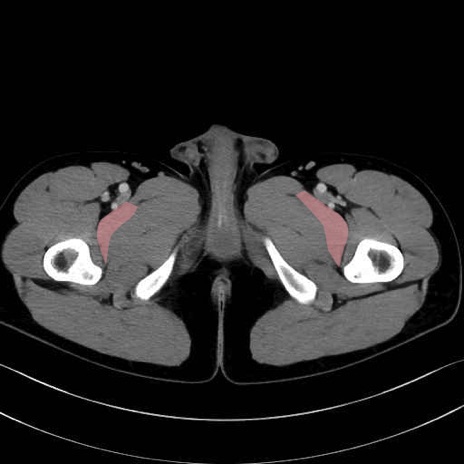

恥骨筋(pubic muscle) のCT画像の解剖

恥骨筋 (Pectineus)